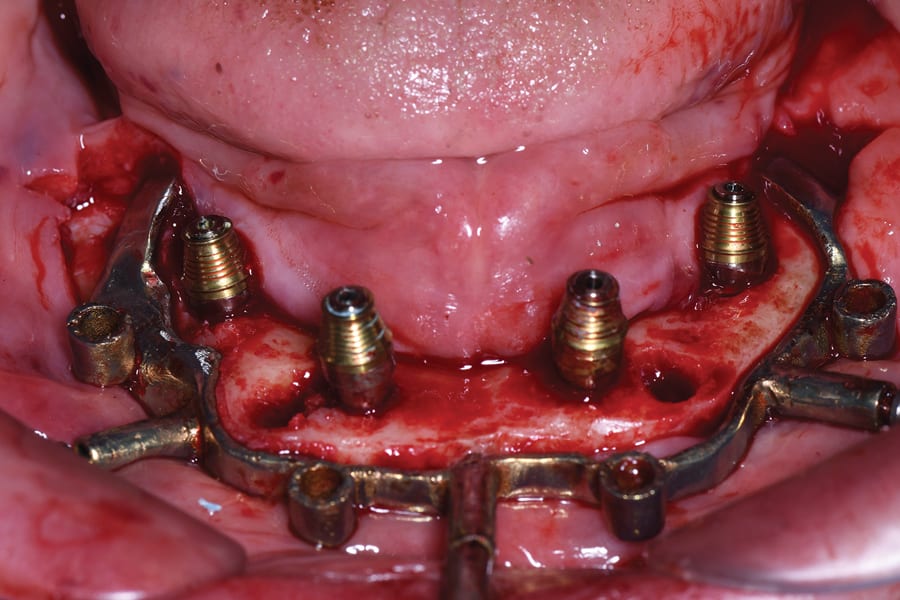

Following bone reduction, with the bone reduction guide still in place, the implant drilling guide was seated over the pin connectors of the bone reduction guide (Figure 5). The osteotomies were prepared, and four 4.3 mm x 13 mm implants (NobelActive®, Nobel Biocare) were placed using a fully guided kit (Guided Drill Guide, Nobel Biocare) with good initial stabilities (40 Ncm to 70 Ncm).

Following implant placement, the implant drilling guide was removed from the pin connectors of the bone reduction guide. Two straight anterior and two 17-degree angled transmucosal multi-unit abutments (MUAs) (Nobel Biocare) were inserted and torqued according to the manufacturer's instruction (Figure 6). Custom-made ti-bases that were compatible with the Nobel MUAs were placed on the MUAs, then fastened by prosthetic screws with finger-torque pressure (Figure 7).